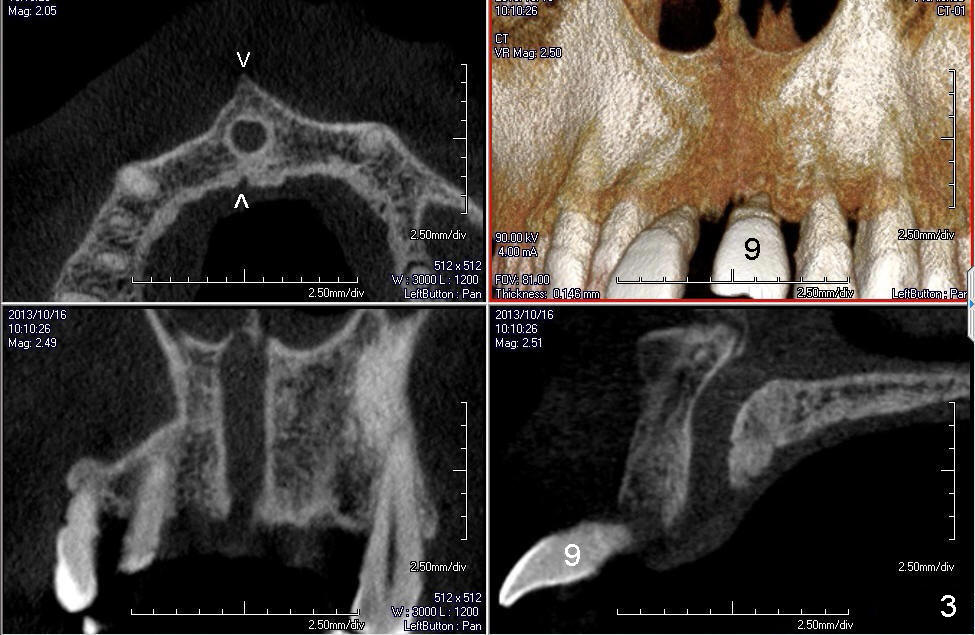

CT研究表明当切牙管小时(图一:I(Incisive Canal),二毫米左右),它比较对称,位于中切牙牙根之间(8,9)。当它大时(五六毫米),它可能对称(图二)或者不对称(图三,四),接近一个(图三,四)或者两个(图二)牙根,造成植牙困难。